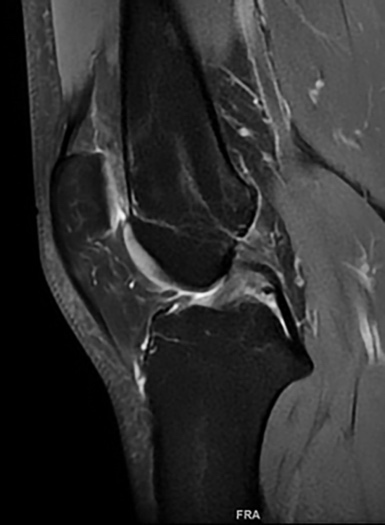

La resonancia magnética permite visualizar los LMFs sin necesidad de disección anatómica. En RM, con cortes en densidad T2, el LCP normal aparece como una estructura uniforme bien definida con una señal de intensidad baja. Cuando está relajado en extensión muestra una curva de convexidad posterior. Una estructura pequeña redonda u oval de baja intensidad se puede apreciar, a menudo, por delante o por detrás del LCP; son los LMF que discurren oblicuamente desde el cuerno posterior del menisco lateral al cóndilo medial [19] (Figura 5) (Figura 6).

Figura 5. A, b, c) RM. Corte sagital rodilla. LMFa

Figura 6. RM. Corte sagital. LMFp